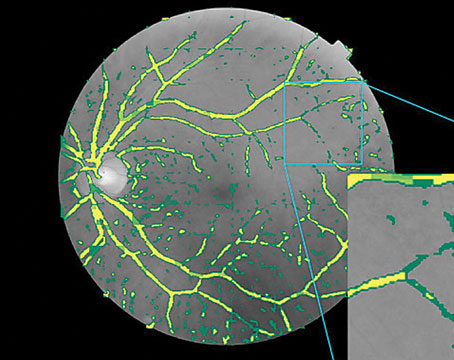

AI in retina: Ready for prime time?

Artificial intelligence is ready to be incorporated into retina referral networks. Here’s a look at the state of the science.